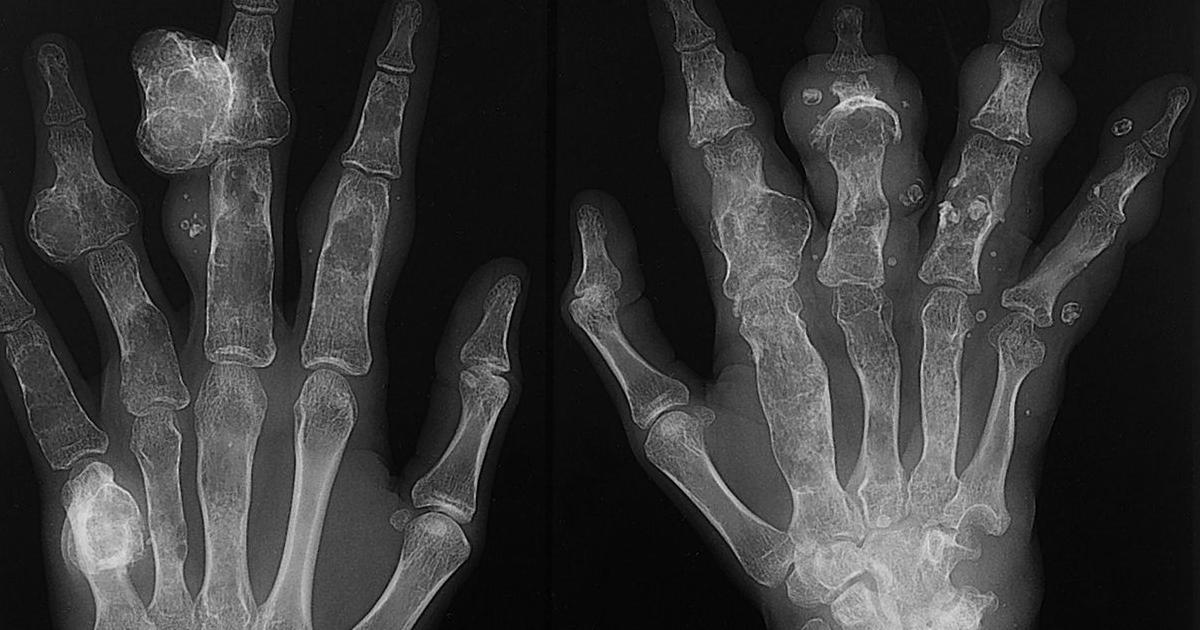

Ollier disease is a condition where multiple benign or noncancerous cartilage tumors called enchondromas develop throughout the skeletal system of the body. A spontaneous mutation in the genes causes Ollier disease to develop. This gene mutation is not one that spreads through families or is inherited. Instead, it happens randomly to an individual in utero or before they are born. The enchondromas that develop in Ollier disease patients are a result of the cartilage cells expanding in an abnormal location. This irregular growth can happen in the form of a projection from a bone, or it can occur inside of a bone. Additional DNA mutations may occur in individuals who already have the gene mutation that causes Ollier disease that accounts for the mechanism that causes enchondromas to become cancerous. When enchondromas become cancerous, they are considered chondrosarcomas. It is not uncommon for one or more of the benign tumors in individuals with Ollier disease to become malignant or cancerous over some time, so Ollier disease patients are at an increased risk for developing chondrosarcoma.

Maffucci syndrome is a disorder where multiple benign or noncancerous cartilage growths develop inside of the bones, and purplish or red growths develop in the skin. Much like Ollier disease, Maffucci syndrome is caused by a gene mutation, and individuals affected by it are at a higher risk of developing chondrosarcoma. Maffucci syndrome enchondromas develop near the part of the bones where growth typically occurs. Benign tumors usually stop becoming larger when the individual with Maffucci syndrome stops growing. While it sounds similar to Ollier disease, Maffucci syndrome has two distinct elements that do not occur in Ollier disease patients. Hemangiomas are skin growths containing tangles of irregular blood vessels that also happen in individuals affected by Maffucci syndrome. In addition, masses that contain tangles of the thin tubes where lymph fluid travels or lymphangiomas develop in Mafucci syndrome patients. Both hemangiomas and lymphangiomas can grow anywhere on the body. Additional mutations that occur alongside the Maffucci syndrome mutation are responsible for some of the enchondromas becoming malignant, resulting in chondrosarcoma.